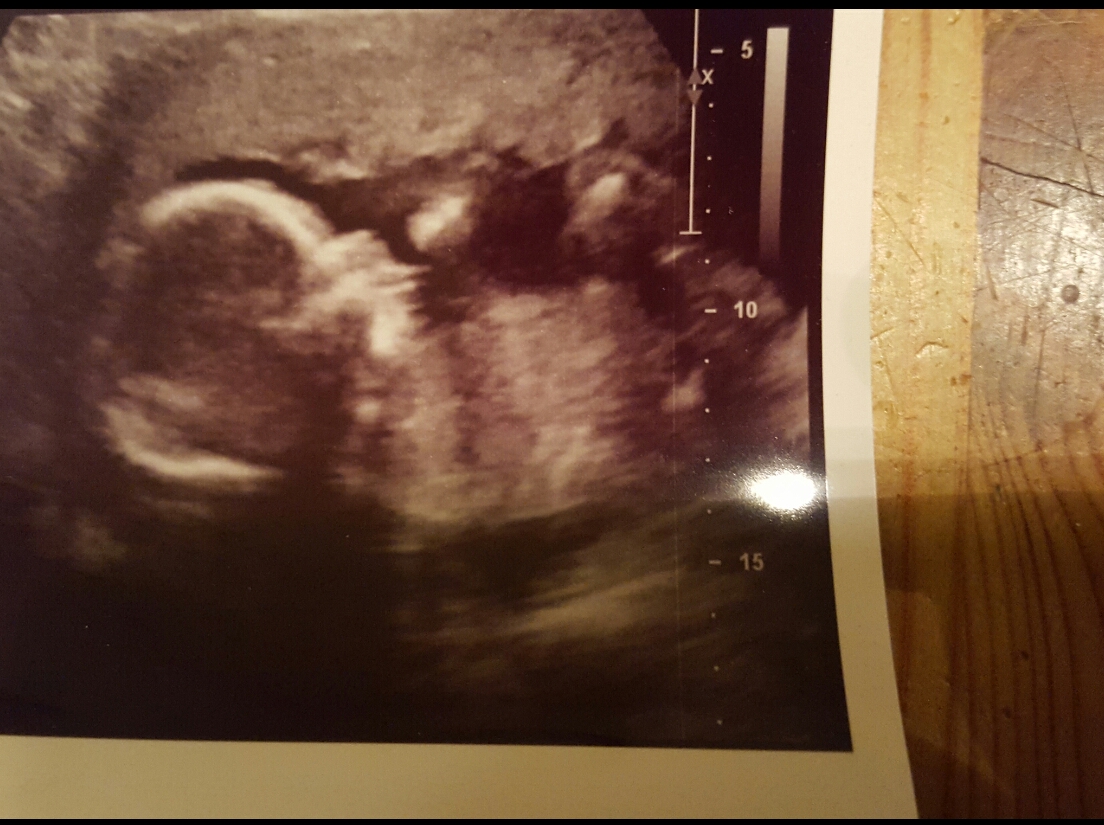

That last pic *might* be showing a girly nub, but I really don't want to give you too much hope. You could post the other pics if you have any more, you never know if there is a better nub shot among them.

İt's a boy!

I was gonna guess boy from ur first pic u can see the little man parts .. congrats